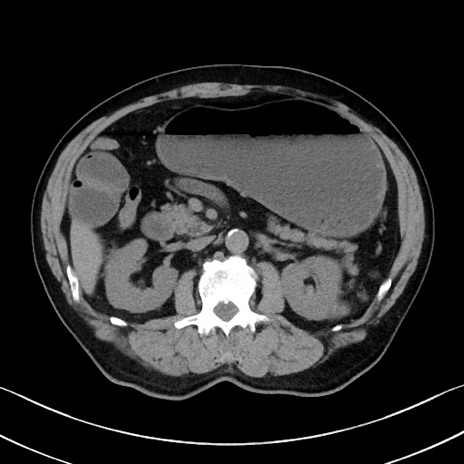

症例35(横断像)

【症例】70歳代 男性

【主訴】腹部膨満、嘔吐

【現病歴】昨日より腹部膨満感出現。本日増悪し、仙痛出現。嘔吐あり、受診。

【既往歴】糖尿病、胆摘後

【身体所見】BP 149/80mmHg、HR 74/min、BT 35.9℃、腹部:膨満、軟、圧痛なし。腸雑音減弱あり。上腹部正中切開瘢痕あり。

【データ】WBC 13500、CRP 1.72